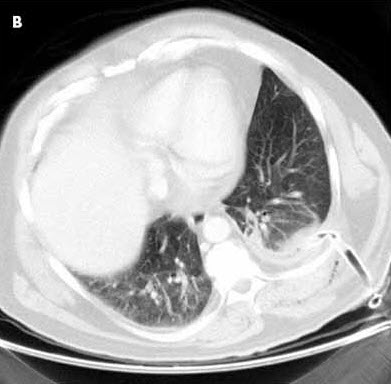

The posteroanterior chest radiograph suggests a rounded retrocardiac density in the left hemithorax (Figure 1). This is confirmed by the lateral view, which shows a large posterior lobulated shadow (Figure 2). The differential diagnosis at this point includes loculated pleural effusion, lung abscess without an air-fluid level, and thoracic empyema with or without an underlying malignancy. A chest CT scan delineates a 9 3 8-cm rounded density (Figure 3). The difference in homogeneity suggests a walled-off fluid collection with no evidence of air.

Intravenous levofloxacin and clindamycin are initiated in anticipation of percutaneous chest tube insertion into the lesion in the left hemithorax. The pleura in the left posterior lung base is slightly thickened; however, there is no evidence of an endobronchial obstructing lesion, hilar-mediastinal mass lesion, or pulmonary nodule. After the tube is placed, about 850 mL of foul-smelling brown fluid is evacuated by gravity (Figure 4). Microbiologic culture of the contents reveals Streptococcus intermedius, which is sensitive to levofloxacin. Cytologic analysis of the drainage material reveals no malignancy. Intravenous levofloxacin is continued for 10 days, followed by oral levofloxacin for another 2 weeks. Chest radiography and chest CT are repeated just before the chest tube is removed to assess whether surgery is needed. The CT scan shows almost complete resolution of the empyema.